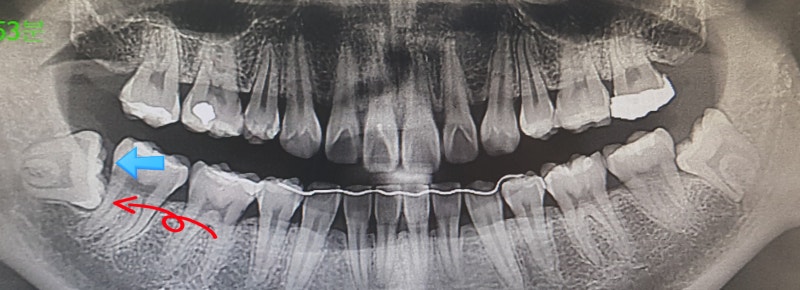

매복 사랑니 1차 발치에 이어 매복 사랑니 2차 발치를 진행했습니다.

이번에 발치할 사랑니는 수직형 사랑니인데요 처음에는 그냥 일반 발치처럼 잇몸을 잘라서 뽑았는데 아주 단단하게 붙어있을 수도 있지만 결국은 뽑히지 않습니다. 치아를 깎는 도구를 샀는데, 수직인지도 모르겠고, 저번보다 연마하는데 시간이 많이 걸렸다. 기계적인 소리와 진동에 머리가 떨리지만 시끄럽고 무섭다 사랑니 발치 잘하는 나라에 태어나서 다행이다 부러진 이를 뽑는 것 같은 느낌 가끔은 조금 아프거나 불편할텐데, 하지만 마취보다 낫습니다 바늘이 훨씬 편합니다.